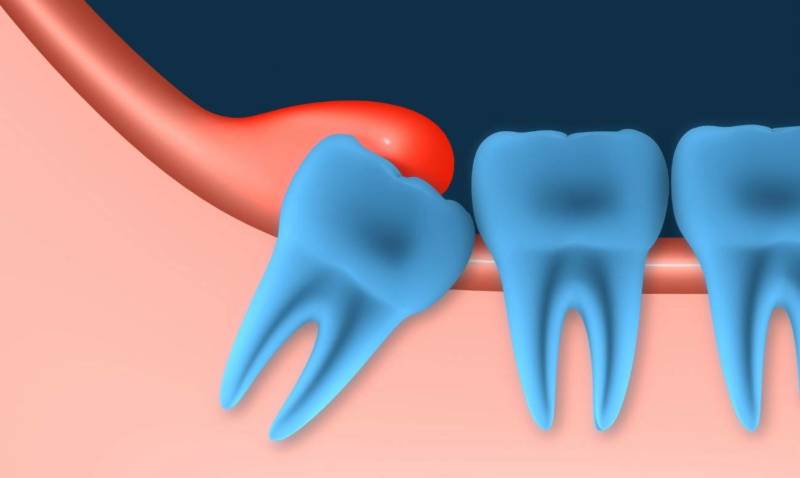

- Во-первых – при недостаточной длине нижней челюсти, что означает отсутствие достаточного места для прорезывания зуба мудрости. Удаление в данном случае позволит предотвратить смещение остальных зубов прорезывающимся зубом, и не даст развиться скученности зубов в переднем отделе нижней челюсти.

- Во-вторых – если 8-ой зуб имеет сильный наклон в сторону щеки или седьмого зуба, то его все-равно рано или поздно придется удалять, т.к. он будет травмировать либо слизистую щеки, либо корень 7-го зуба, соответственно.

- На челюстной дуге не хватает места, чтобы третий моляр мог прорезываться безо всяких осложнений. Единица удаляется, если ее рост идет в неправильном направлении.

При неправильном росте третий моляр сдавливает семерки и становится причиной их преждевременного разрушения. В отдельных случаях зубы мудрости упираются в мягкие ткани щеки, что также приводит к воспалительным процессам во рту и болезненности десен.